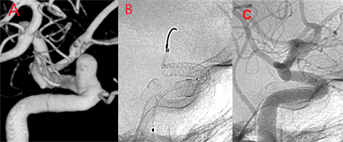

隨著醫療技術的進步,針對開口大的動脈瘤、形狀位置刁鑽或是大型的動脈瘤(直徑超過1.5公分以上),可利用具有導引血流功能的血管導流裝置(Flow diverter)治療,血管導流裝置看似一個編織細密的支架,置放後可藉由血流導向,降低血流直接衝擊動脈瘤的力道,經過一段時間,更可以促進血管內皮再生,覆蓋動脈瘤的開口,徹底讓動脈瘤消失。

本院自2014年就開始應用這項治療技術,也是這項技術在台灣的示範教學中心,截至目前2023年本院使用導流裝置治療動脈瘤的成功率將近100%,術後追蹤動脈瘤閉塞率高達九成,此外有超過半數以上的患者,經追蹤評估後,有機會不再需要每天服用一般支架放完後,所需服用的阿斯匹林(Aspirin)及保栓通(Plavix)…等抗血小板的藥物,大家對於這項治療接受度越來越高。

(A)內頸動脈眼動脈段,有一7x5-mm未破裂的動脈瘤;(B) 患者接受血流導向裝置治療;(C) 半年後門診血管攝影追蹤,動脈瘤完全消失,眼動脈暢通且內頸動脈無明顯狹窄